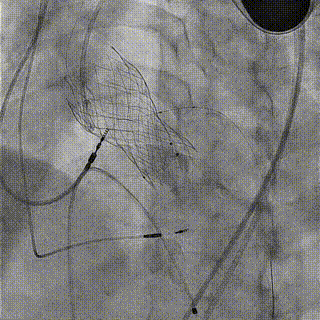

手术过程

1.LAD+LCX造影

2.右冠造影

3.主动脉根部造影

4.18mm球囊预扩

5.跨弓+跨瓣

6.释放至工作位

7.完全释放

8.术后造影,冠脉血流通畅

瓣膜释放后,复查左室-主动脉瓣峰值压差0-1mmHg,食道超声及造影像均提示瓣膜无反流,冠脉血流通畅。